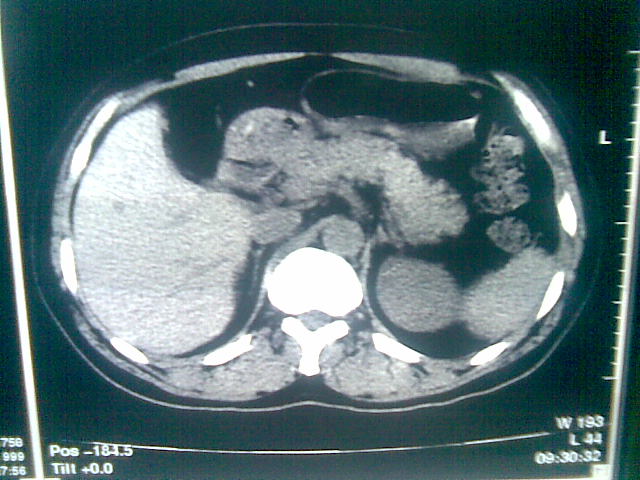

标题: CT23981:男,38岁阑尾炎术后透视胸腔积夜!做CT如下!积液包 [打印本页]

标题: CT23981:男,38岁阑尾炎术后透视胸腔积夜!做CT如下!积液包

可能与阑尾术后关系不太大,1.胸膜增厚粘连见少量气体。包裹脓气胸?左侧网膜囊脓肿?

.胸膜增厚粘连见少量气体。包裹脓气胸

左侧胸膜增厚、粘连+包裹液气胸。